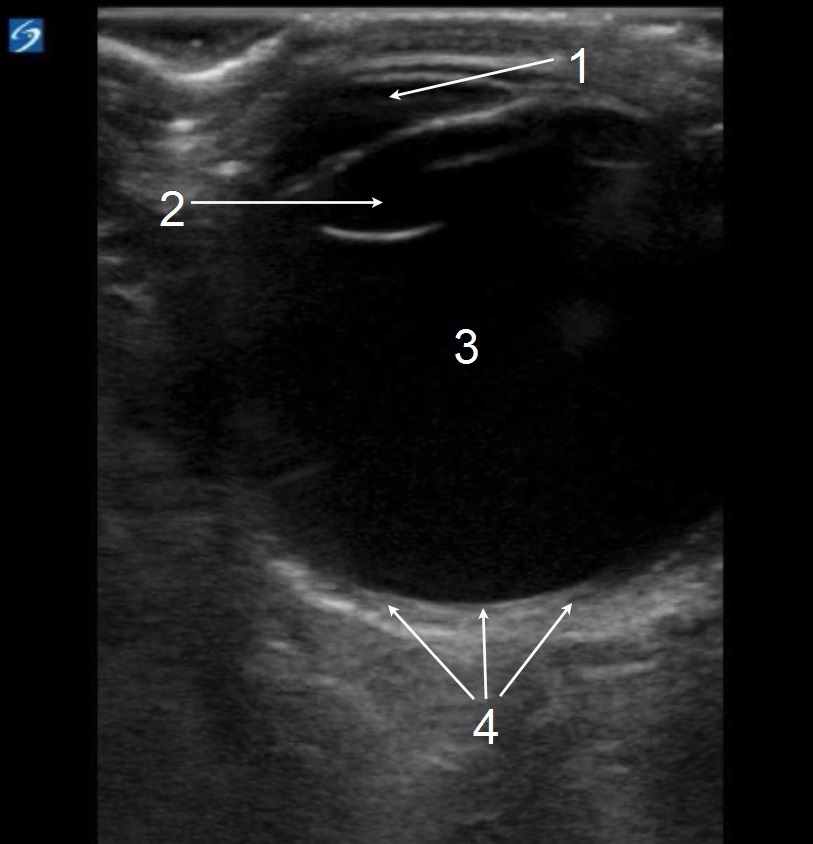

眼部正常解剖结构 4 图像

前房

视网膜

玻璃体

晶状体